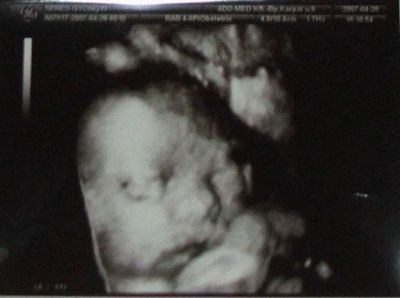

Kép Kép Kép

Ő a mi kisfiunk,itt 28 hetesek voltunk!